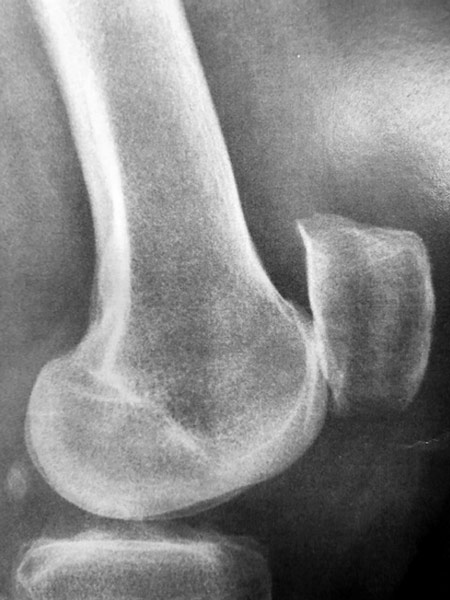

Arthrose externe de rotule isolée chez une patiente jeune, âgée de 45 ans.